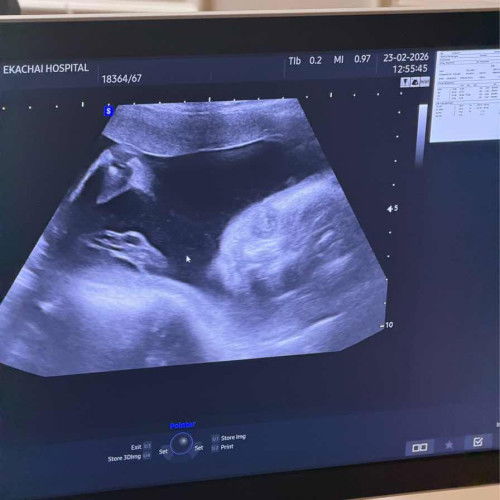

บ้านนี้ท้องที่2ได้16weekแล้วค่ะ ท้องแรกไม่มีปัญหาหรืออาการแซกซ้อนใดๆ แต่ท้องนี้กังวลมากค่ะกลัวน้องหัวใจหยุดเต้นบ้างหรือเสียชีวิตในครรภ์บ้างกลัวหลุดบ้างเพราะมีอาการปวดท้องหรือปวดหน่วงบ่อยค่ะ+กับเสพสื่อใน ตต กับเรื่องพวกนี้ด้วยค่ะ#ขอคำแนะคำปรึกษาคะ #ขอบคณสำหรับคำตอบล่วงหน้านะคะ #ขอบคุณสำหรับคอมเม้นล่วงหน้าค่ะ #ช่วยบอกกันหน่อยนะคะ